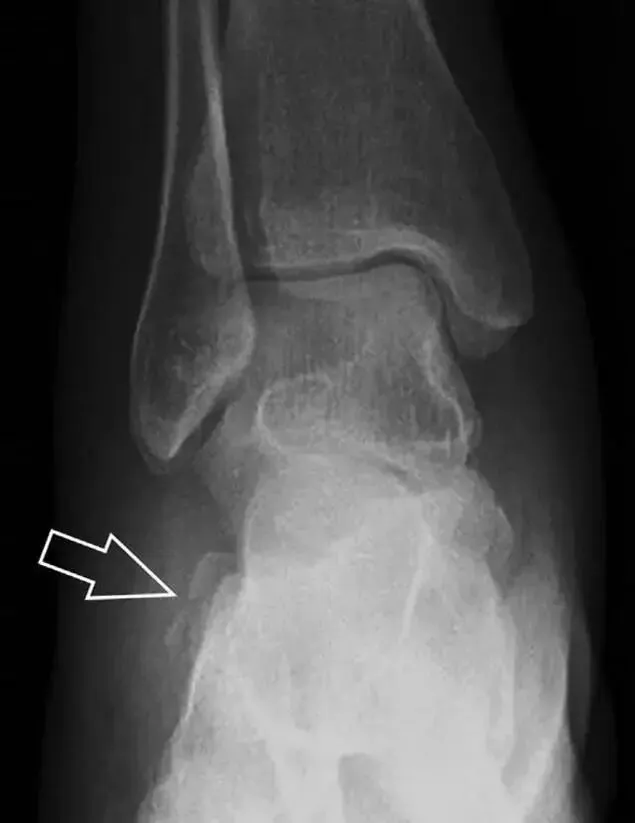

3、距骨外侧突骨折

距骨外侧突骨折常因踝外翻背屈时,跟骨上外侧面撞击距骨外侧突下缘导致,或偶尔由踝内翻引起,被称为滑雪板者骨折。这种骨折只能在踝关节正位片上发现,而且外踝远端表面软组织肿胀往往是一个重要线索。

(如图)距骨外侧突骨折。

A-正位片示内翻损伤所致的距骨外侧突撕脱性骨折(箭头)。

B-另一位患者,踝外翻损伤导致典型的[滑雪板者骨折],X 片上可见一较大的三角形骨折块(方框)。